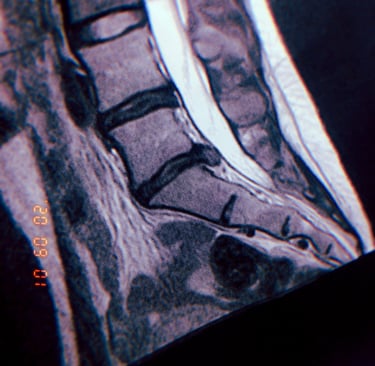

< MRI scan showing a herniated disc, a common ailment affecting individuals in the riding industry.

Grasping the fundamentals of seat awareness and biomechanics is crucial for preventing a range of health issues, including herniated discs. A herniated disc can lead to debilitating pain, stiffness, and in severe cases, nerve damage that results in a loss of sensation. This not only affects physical well-being but can also significantly diminish one’s overall quality of life.

By learning about proper seating posture and the mechanics of your seat, you can avoid common pitfalls that contribute to these serious conditions. Investing time in understanding how your seat can impact your health is essential for maintaining comfort and preventing long-term complications.